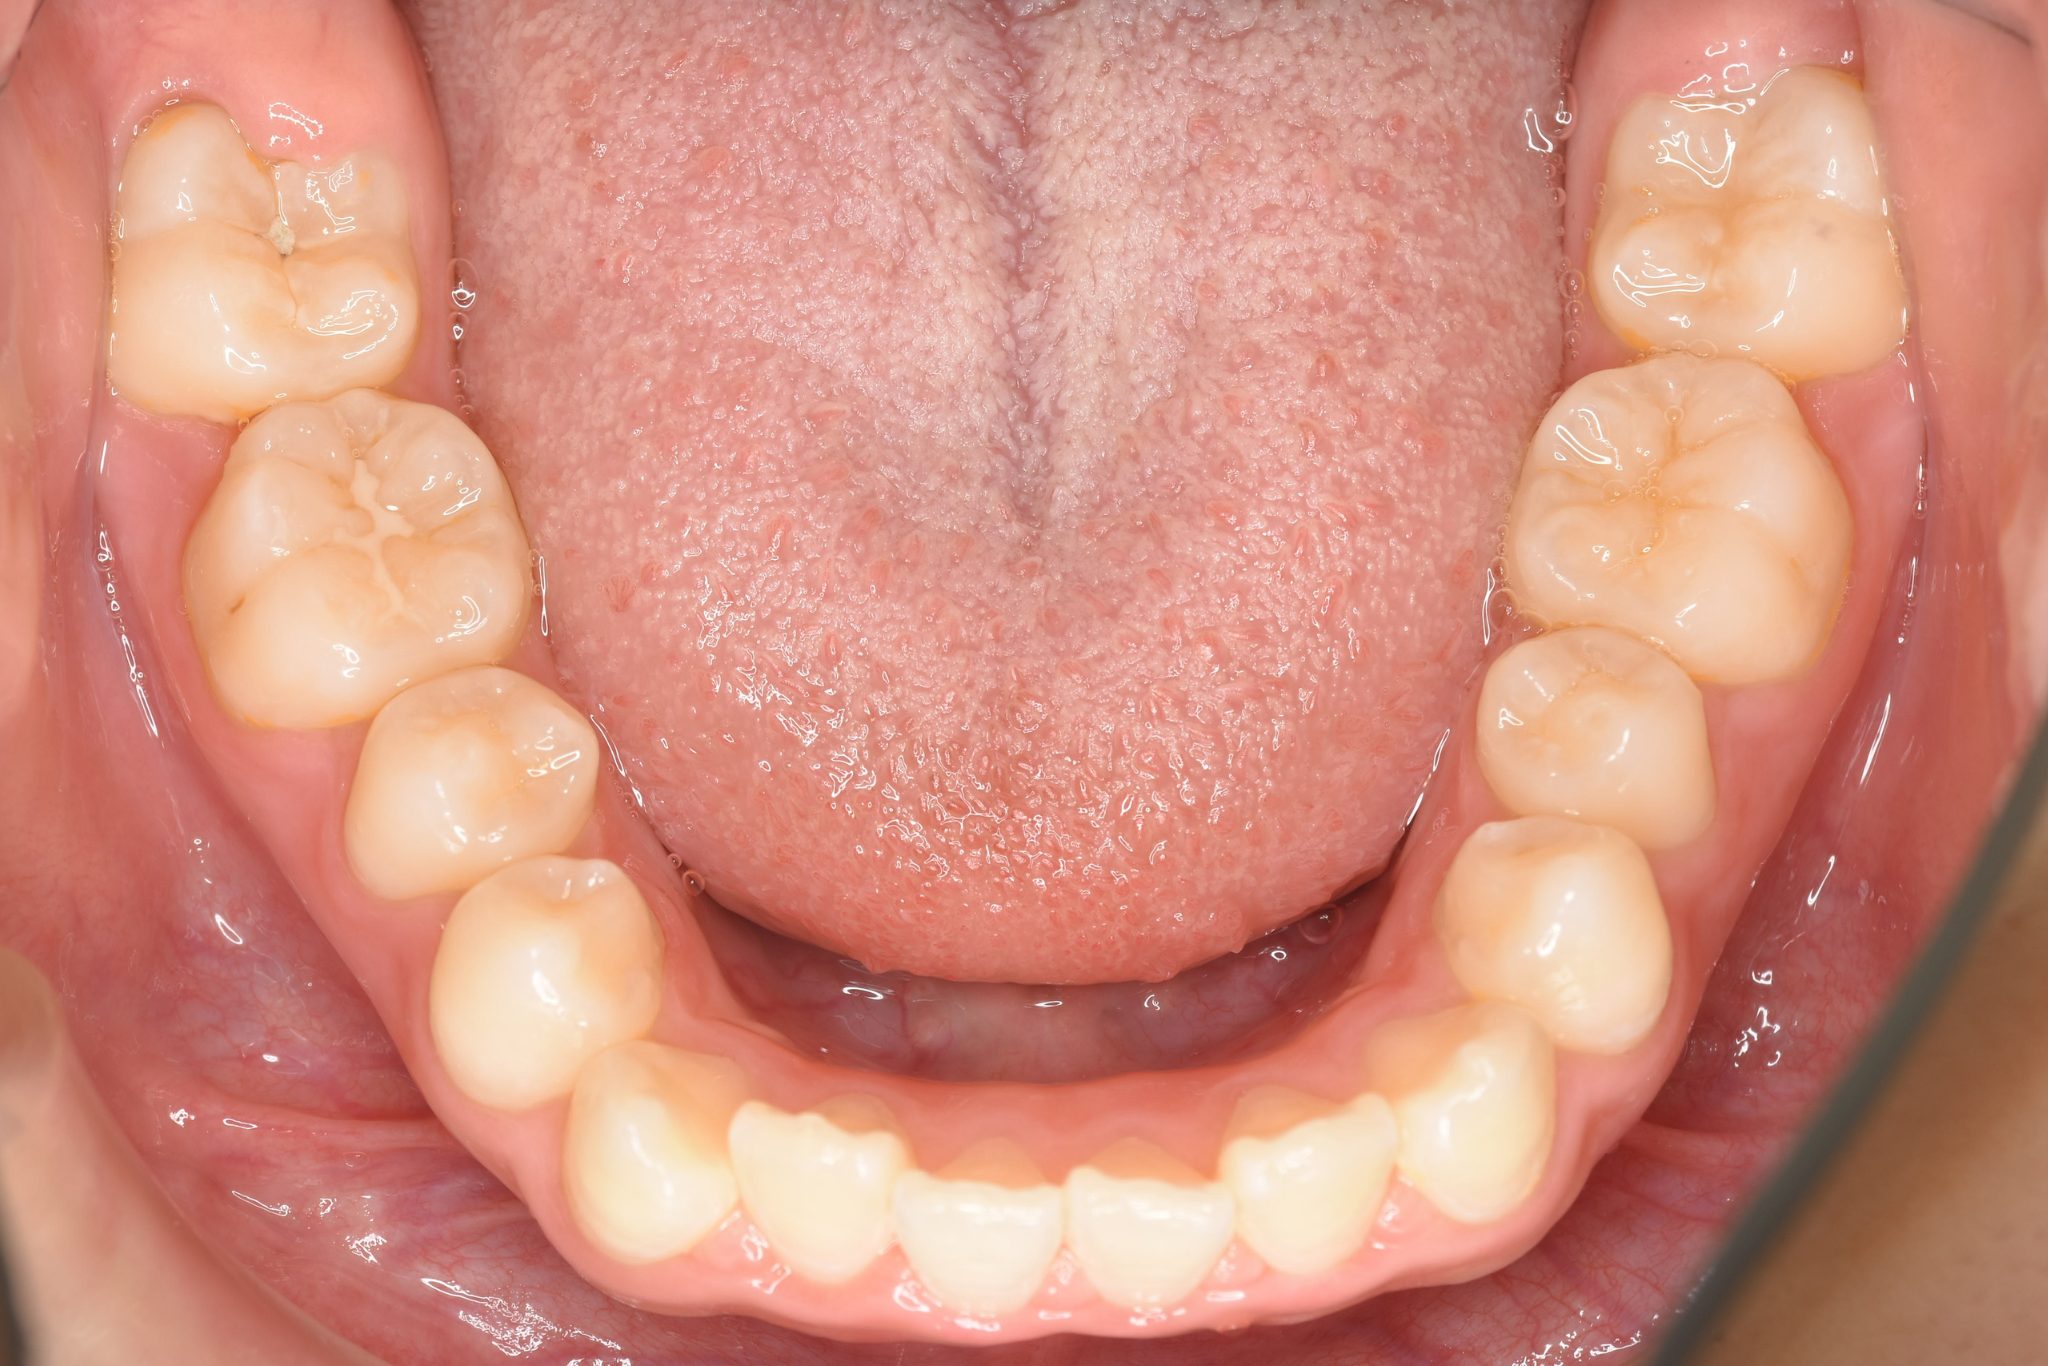

ビフォー

主訴 歯並び|嚙み合わせ|口呼吸

施術内容 上顎急速拡大装置と下顎リンガルアーチを用いて上下顎骨を拡大した。

その後マウスピース型矯正装置で歯牙を配列し良好な咬合を獲得した。

治癒期間 3年5ヶ月間